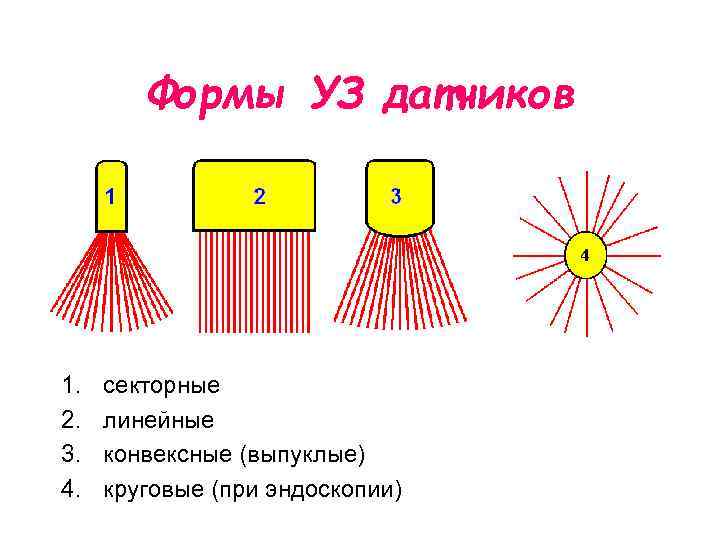

Формы УЗ датчиков 1. 2. 3. 4. секторные линейные конвексные (выпуклые) круговые (при эндоскопии)

Формы УЗ датчиков 1. 2. 3. 4. секторные линейные конвексные (выпуклые) круговые (при эндоскопии)

Линейные датчики 5 -15 Мгц • • полное соответствие исследуемого органа положению самого трансдюсора на поверхности тела. • сложность обеспечения равномерного прилегания поверхности к коже пациента, искажения получаемого изображения по краям. • Высокая разрешающая способность • глубина сканирования достаточно мала (не более 10 см). • Используются в основном для исследования поверхностно расположенных структур - щитовидной железы, молочных желез, небольших суставов и мышц, а также для исследования сосудов.

Линейные датчики 5 -15 Мгц • • полное соответствие исследуемого органа положению самого трансдюсора на поверхности тела. • сложность обеспечения равномерного прилегания поверхности к коже пациента, искажения получаемого изображения по краям. • Высокая разрешающая способность • глубина сканирования достаточно мала (не более 10 см). • Используются в основном для исследования поверхностно расположенных структур - щитовидной железы, молочных желез, небольших суставов и мышц, а также для исследования сосудов.

Конвексные датчики 2, 5 -7, 5 МГц • • равномерность прилегания к коже пациента • получаемое изображение по ширине на несколько сантиметров больше размеров самого датчика. • Более низкая разрешающая способность • глубина сканирования достигает 20 -25 см • Обычно используется для исследования глубоко расположенных органов - органы брюшной полости и забрюшинного пространства, мочеполовой системы, тазобедренные суставы.

Конвексные датчики 2, 5 -7, 5 МГц • • равномерность прилегания к коже пациента • получаемое изображение по ширине на несколько сантиметров больше размеров самого датчика. • Более низкая разрешающая способность • глубина сканирования достигает 20 -25 см • Обычно используется для исследования глубоко расположенных органов - органы брюшной полости и забрюшинного пространства, мочеполовой системы, тазобедренные суставы.

Секторные датчики 1, 5 -5 Мгц • • большее несоответствие между размерами трансдюсора и получаемым изображением • используется преимущественно в тех случаях, когда необходимо с маленького участка тела получить большой обзор на глубине • Наиболее целесообразно использование секторного сканирования при исследовании, например, через межреберные промежутки. Типичным применением секторного датчика является эхокардиоскопия - исследование сердца.

Секторные датчики 1, 5 -5 Мгц • • большее несоответствие между размерами трансдюсора и получаемым изображением • используется преимущественно в тех случаях, когда необходимо с маленького участка тела получить большой обзор на глубине • Наиболее целесообразно использование секторного сканирования при исследовании, например, через межреберные промежутки. Типичным применением секторного датчика является эхокардиоскопия - исследование сердца.